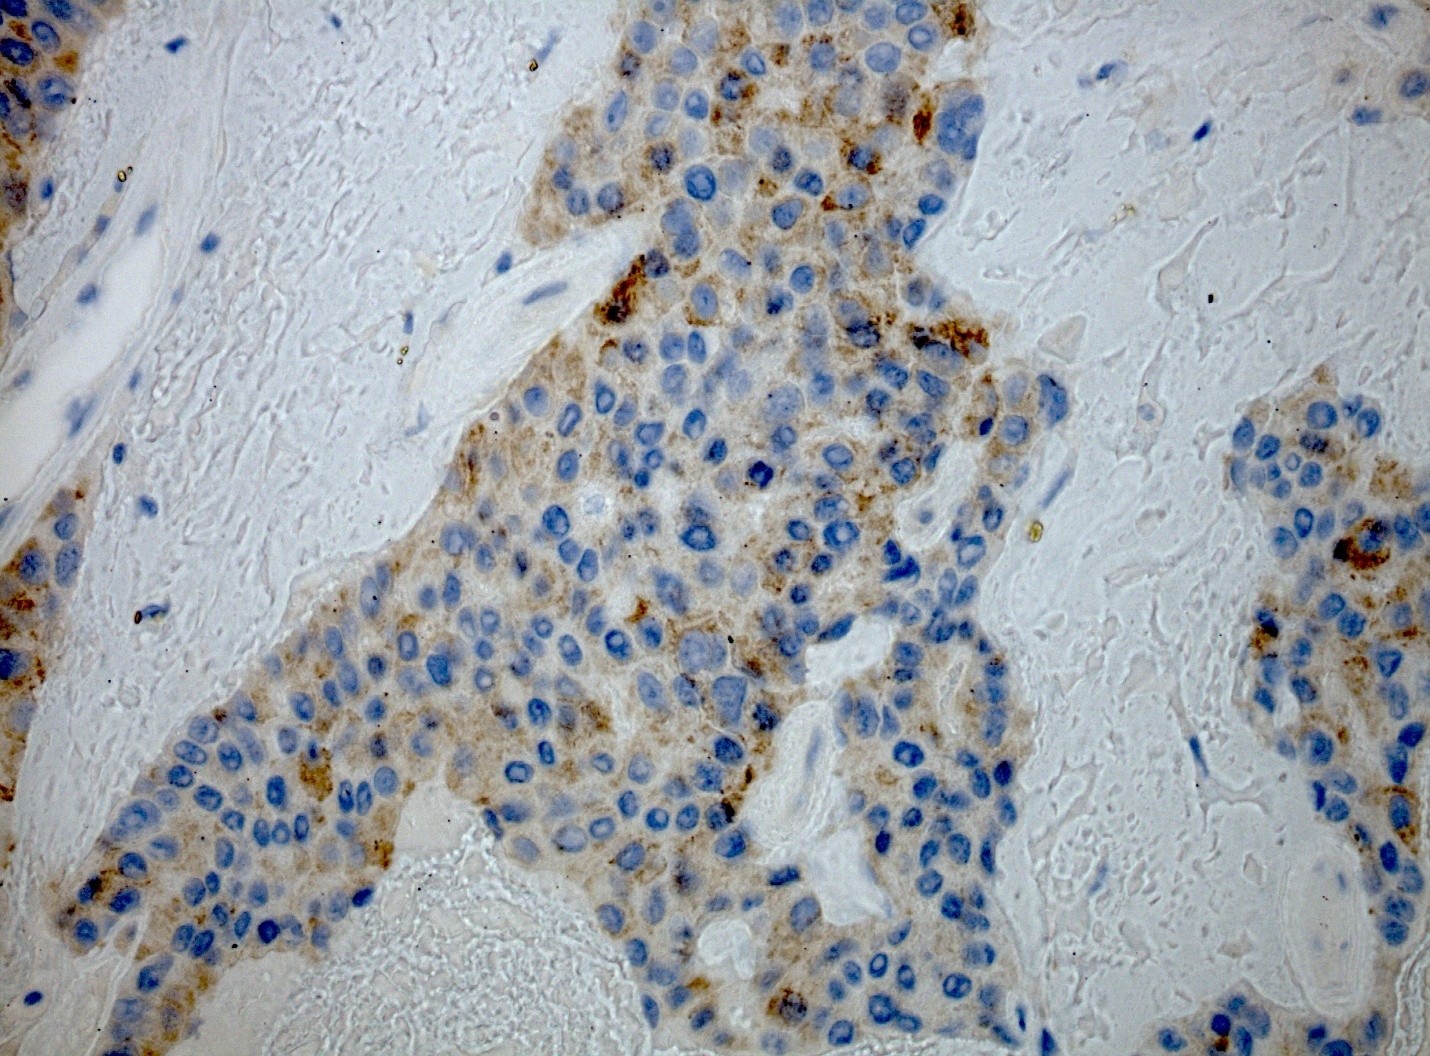

• IHC Staining image

IHC staining of paraffin-embedded HER2 positive breast cancer using IL36G antibody TA505994 clone OTI2F4 mouse monoclonal antibody.